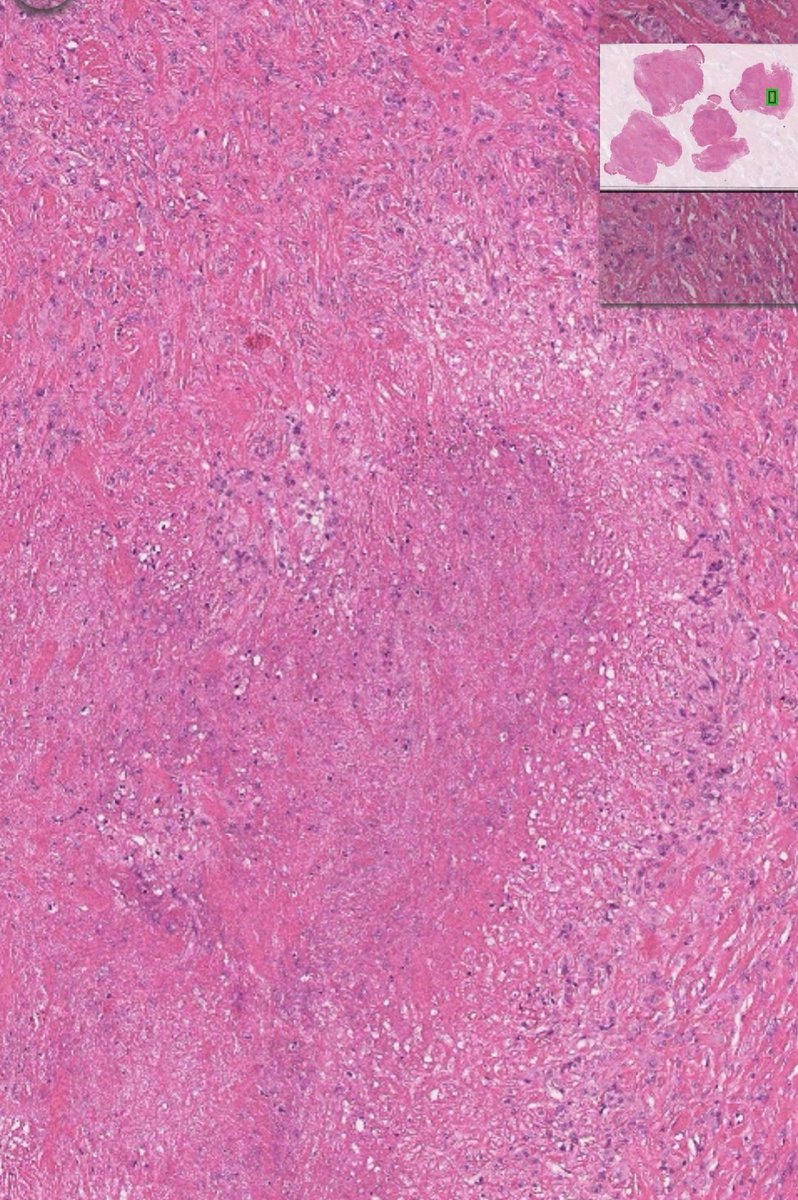

Paris category for urothelial carcinoma #MedTwitter #TwitterPath #GUPath

amnabruno's tweet image. Paris category for urothelial carcinoma

#MedTwitter #TwitterPath #GUPath